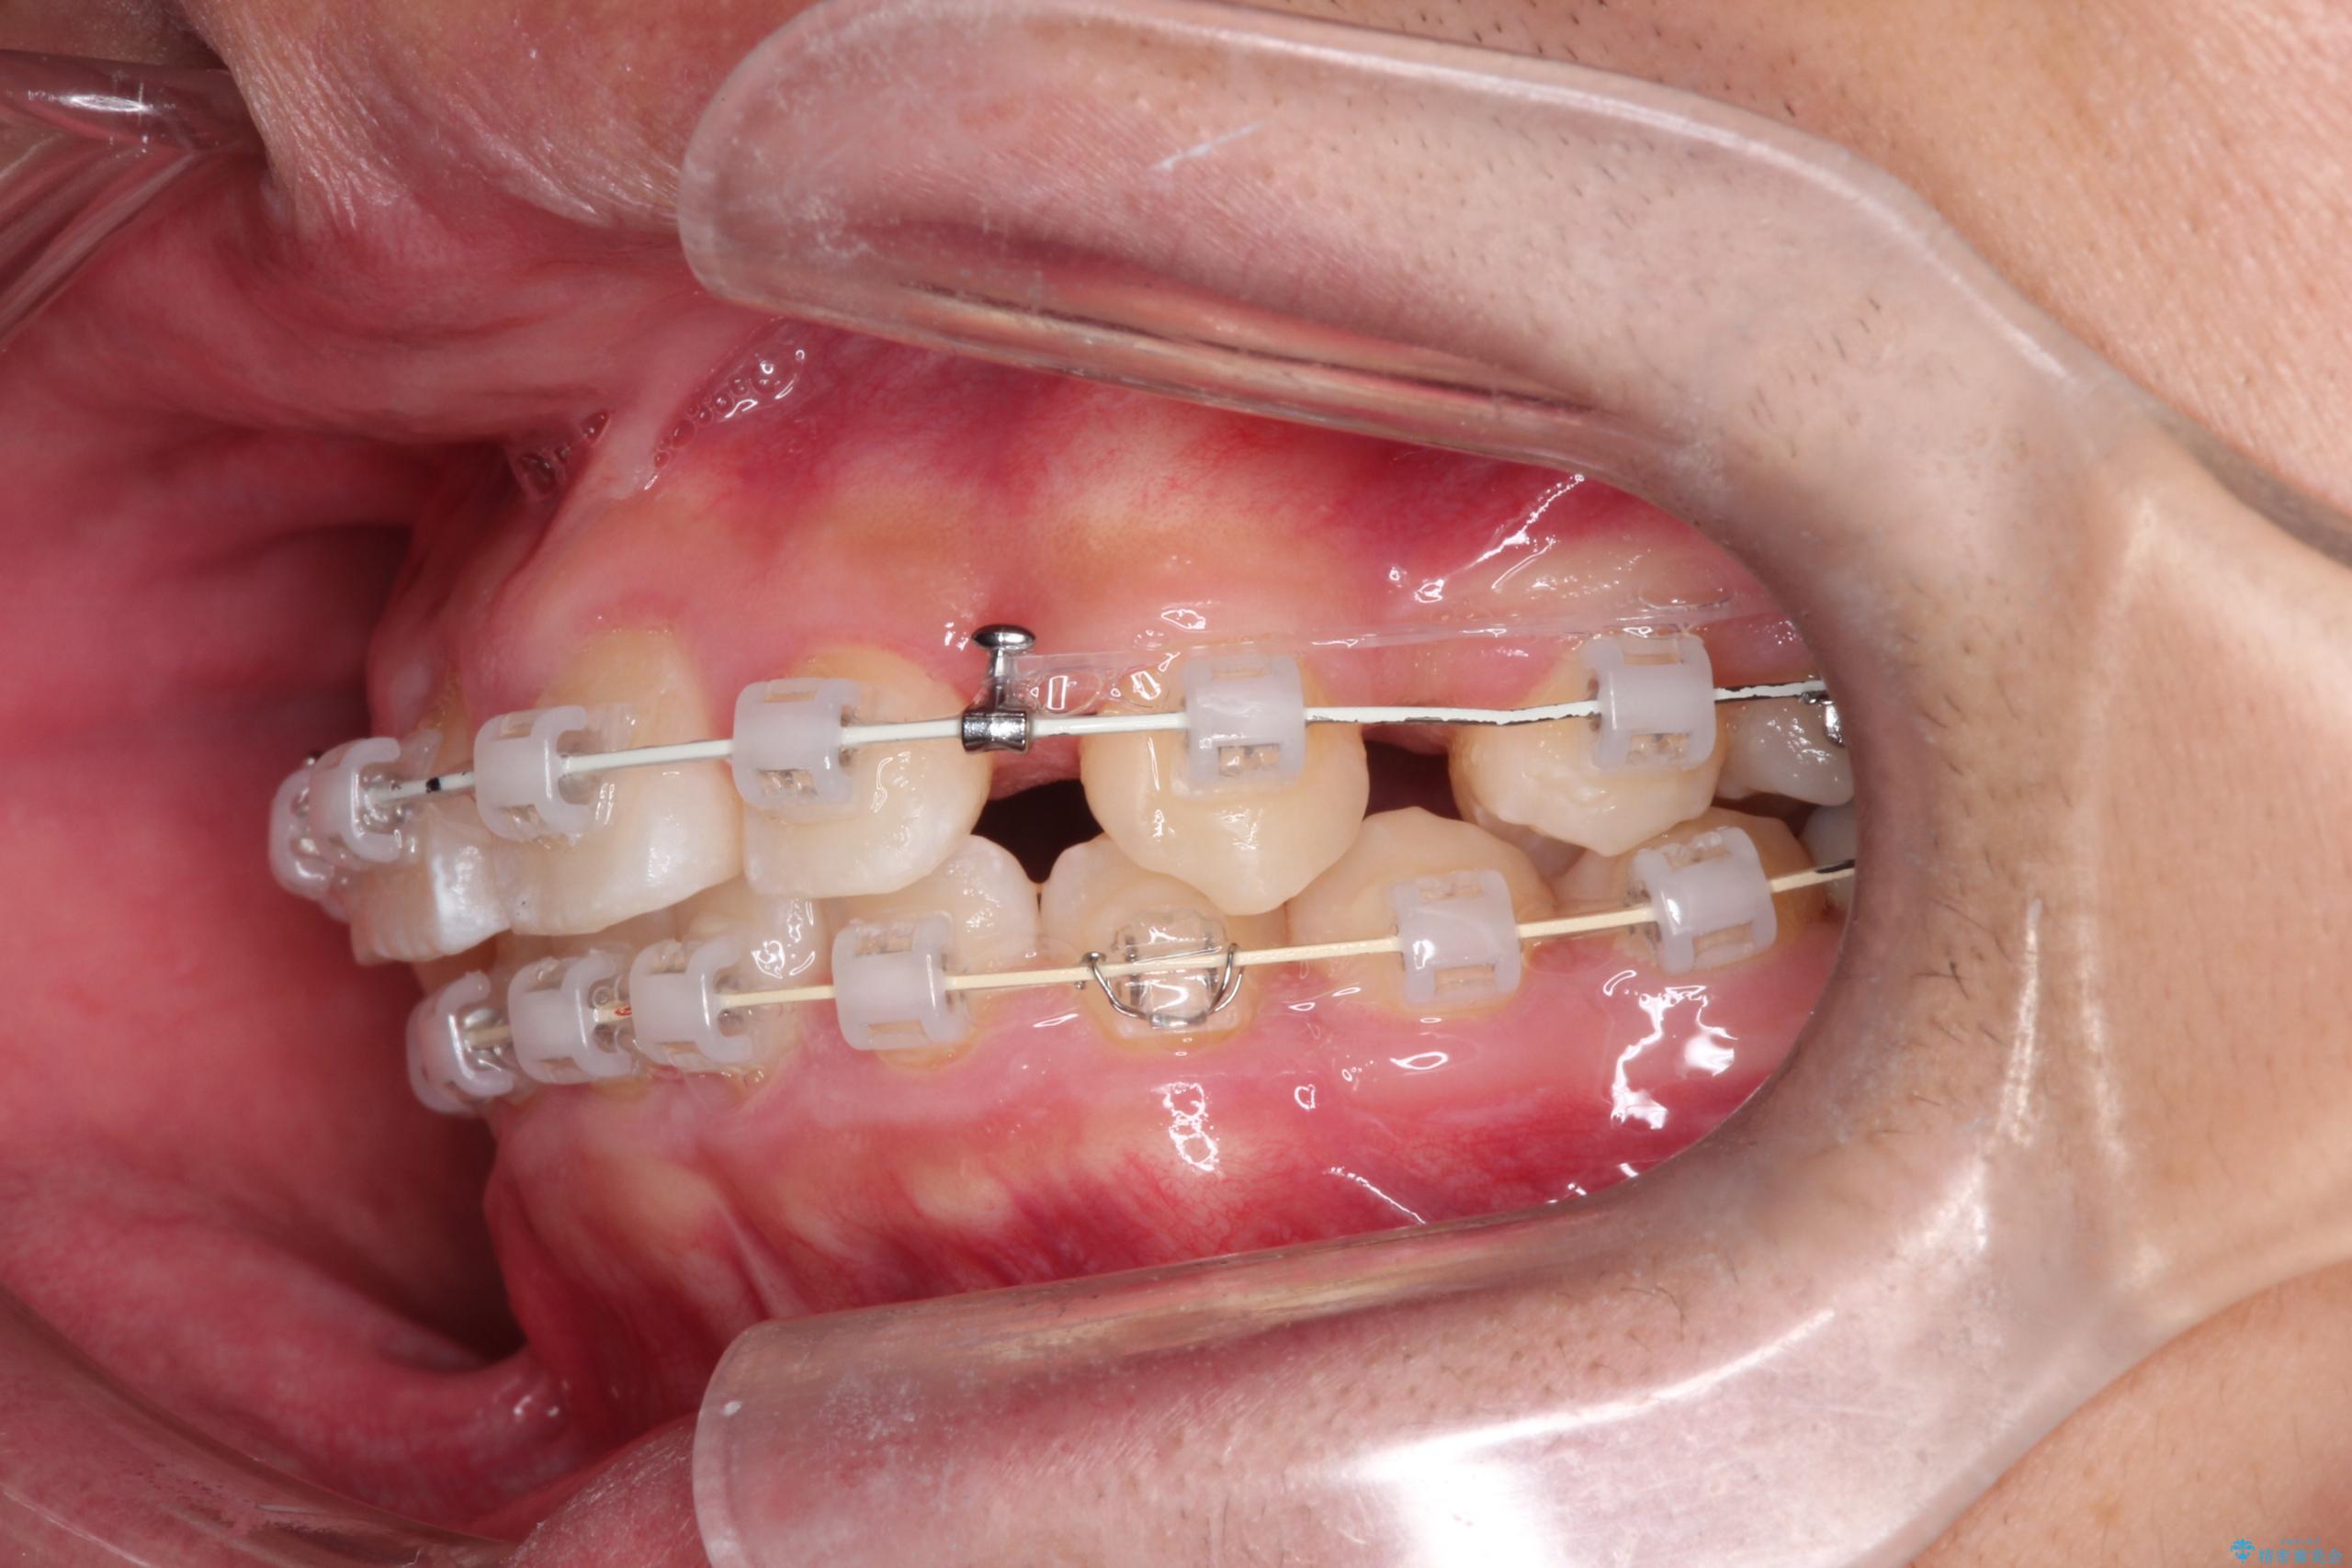

- ワイヤー(審美装置)

矯正の精密検査の結果上顎左右4番の計2本を抜歯し、審美性に配慮したワイヤー矯正装置(審美装置)を用いて治療を行いました。